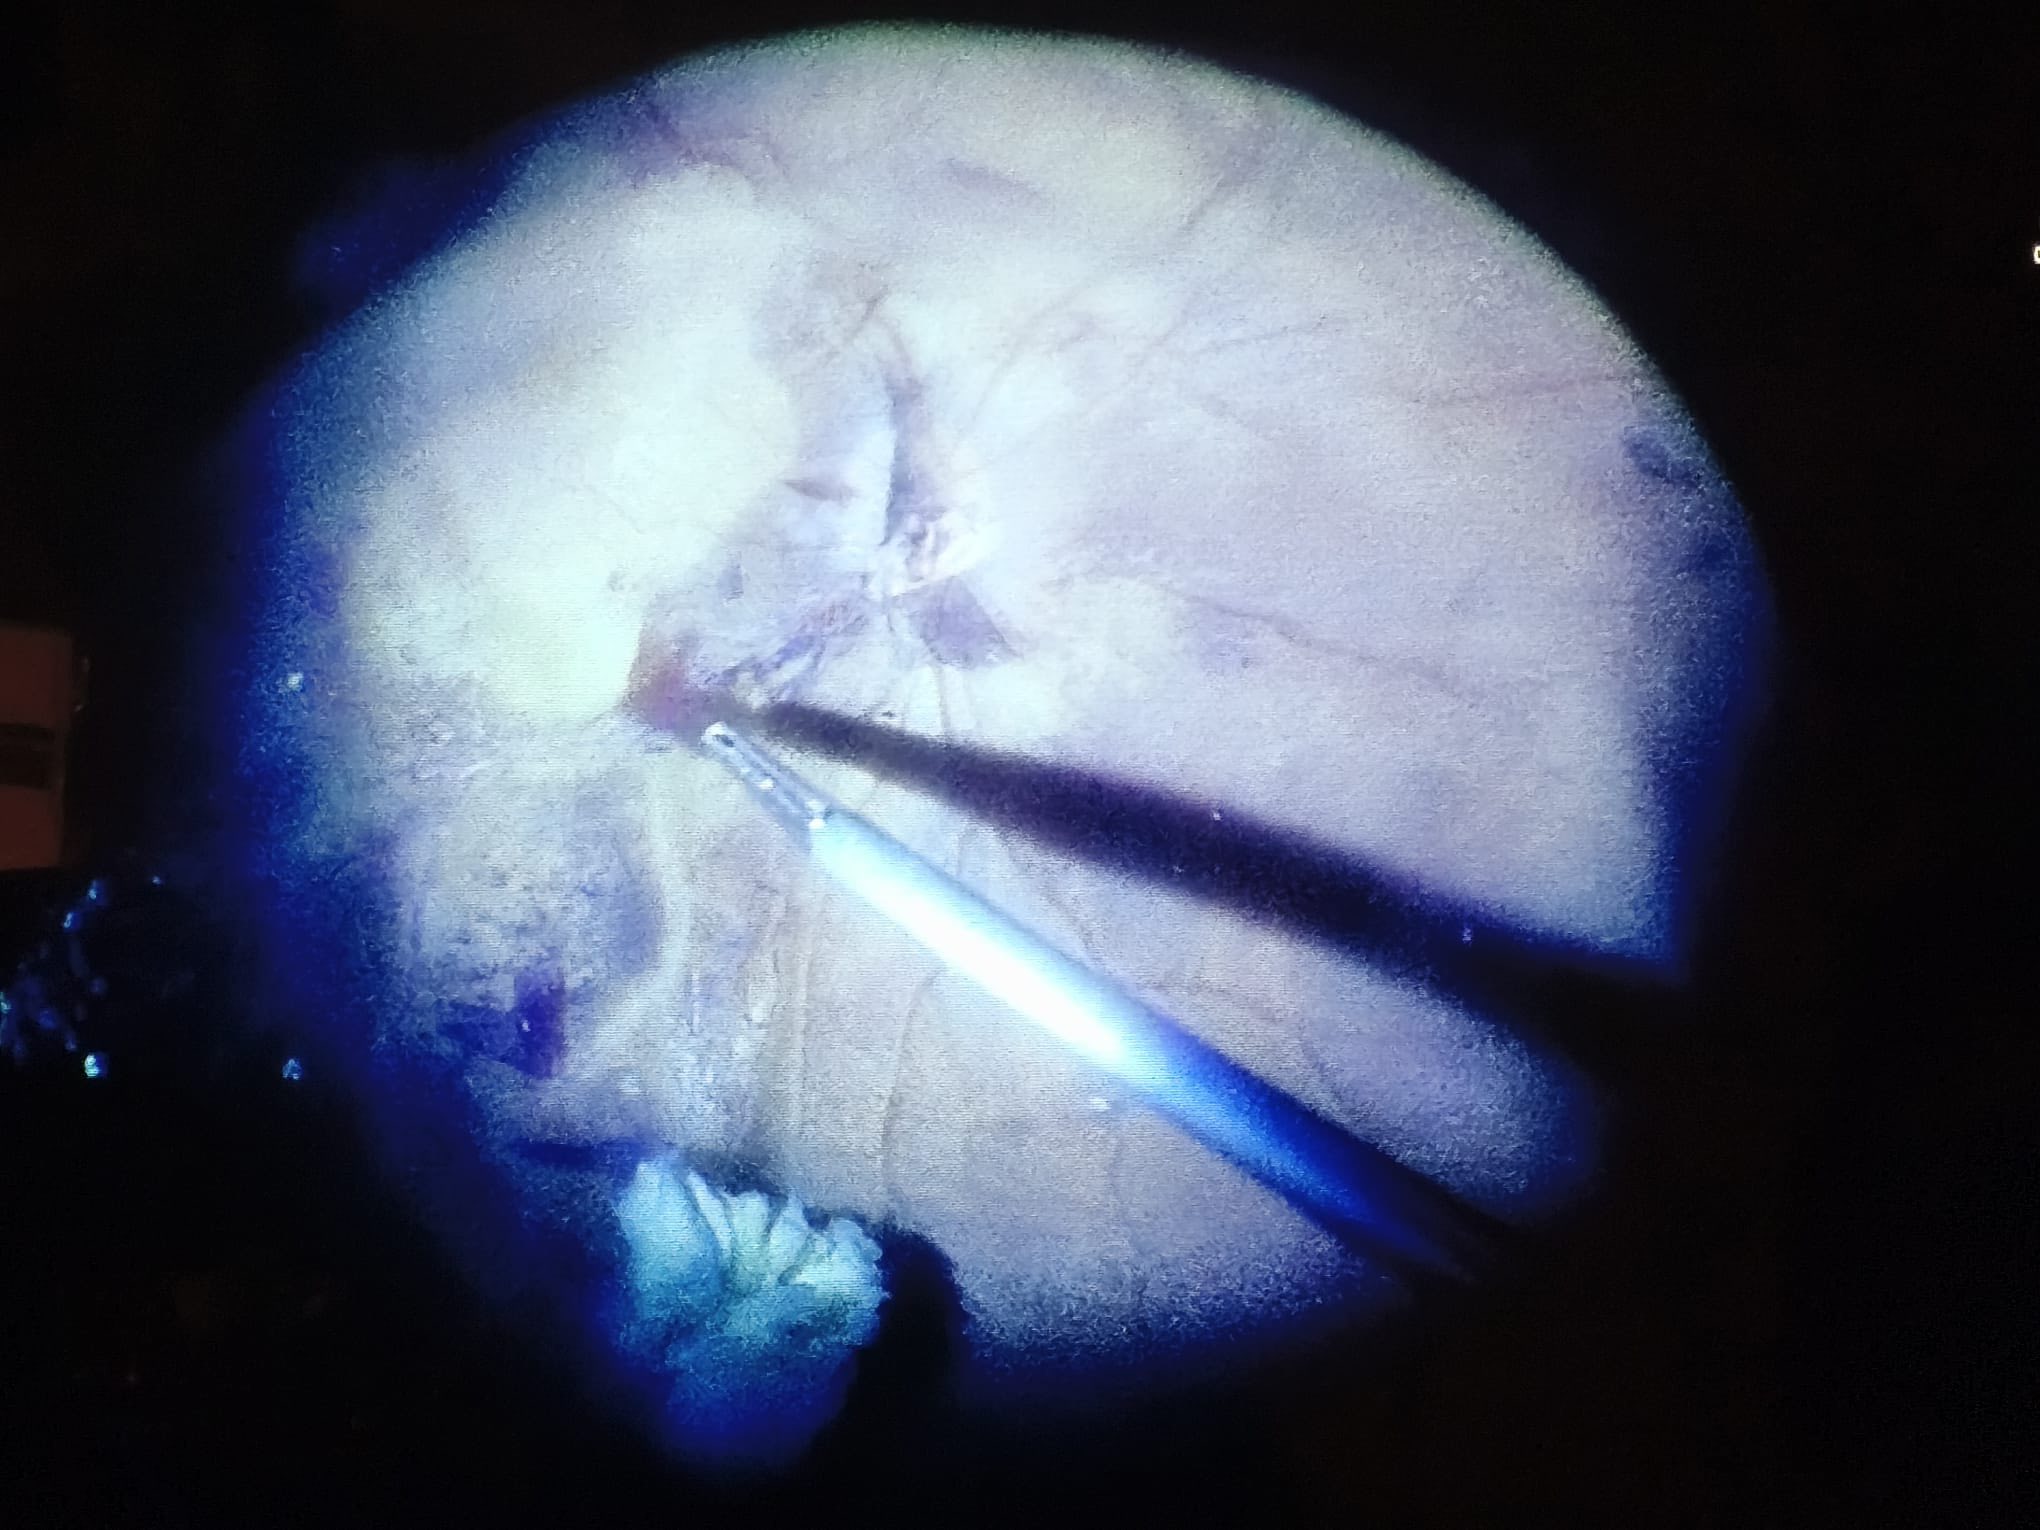

Intraoperator, cauza sângerării masive intraoculare a ieșit la iveală: o ocluzie de ram venos superi-temporal retinian (un fel de “infarct” al unei părți din retină), vasele supero-temporale apărând complet obstruate, fără conținut sanguin, ca niște “sârme” albe, strălucitoare.

Intervenția, efectuată de dr. Ozana Moraru, a fost vitrectomie prin pars-plana, decolarea membranelor fibroase de la suprafața retinei, aplicații endo-laser în jurul dializei retiniene și circular, pe 360 de grade, decolarea membranei ILM din aria maculară și tamponadă cu ulei siliconic.